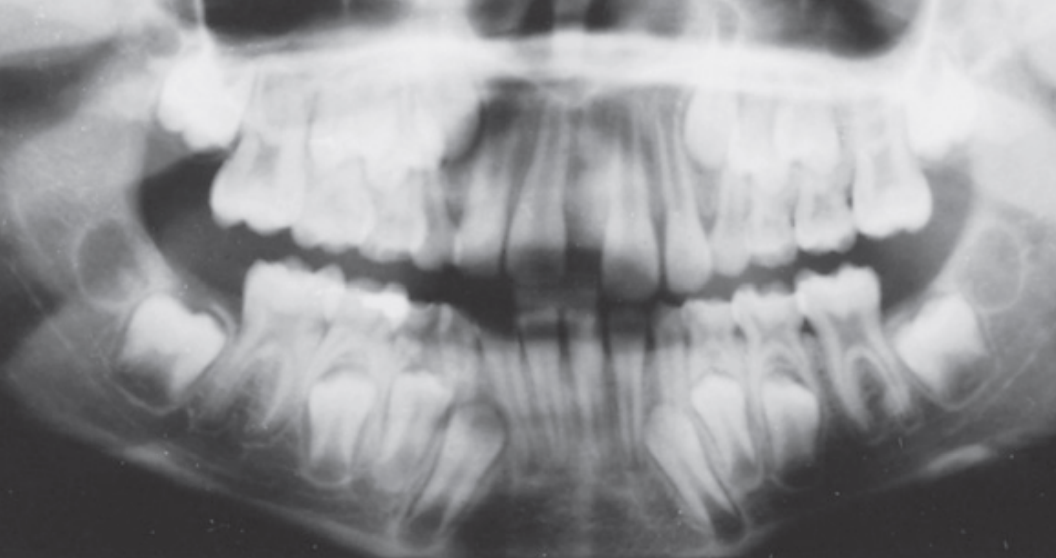

Dental age 9 the maxillary lateral incisors have been in place for 1 year, and

root formation on other incisors and first molars is nearly complete.

Teeth erupted Maxilla 12CDE6, Mandible 12CDE6

Teeth unerupted – Maxilla 3457, Mandible 3457

Dental age 11 is characterized by the eruption of the mandibular canines,

mandibular first premolars, and maxillary first premolars

Teeth erupted Maxilla 12C4E6, Mandible 1234E6

Teeth unerupted – Maxilla 3457, Mandible 57

Dental age 12 is characterized by eruption of maxillary canine and the maxillary and mandibular second premolars.

Teeth erupted– Maxilla 1234567, Mandible 1234567

Teeth unerupted – all 2nd and 3rd molars